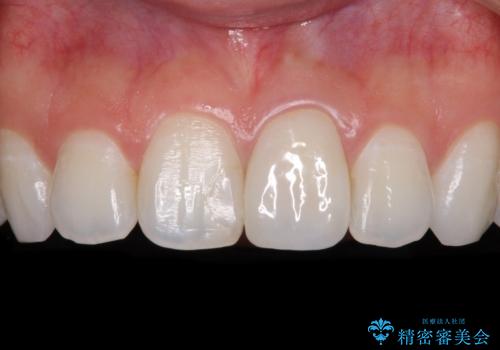

出っ歯に仕上がってしまった前歯 セラミッククラウンの作り替え

- 以前治療した時から、前歯のセラミックが張り出しているのが気になるとのことで来院された患者様です。

作り替えるべきが悩みましたが、どうしても気になるとのことで、処置を行うこととしました。

前歯1歯でのオールセラミッククラウンでは、オーダーメイドタイプのクラウンを選択していただき、周辺の歯と色調を合わせるようにするのですが、今回は既製タイプを選択されました。